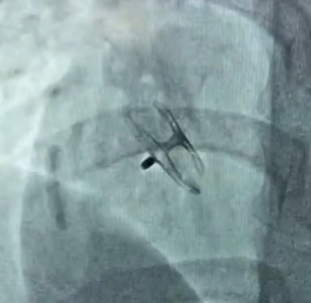

卵圆孔隧道长12mm,裂隙直径3.2mm。房间隔探及左向右约4mm的分流束。应用D-shufo 3036-6 PFO封堵器成功封堵。